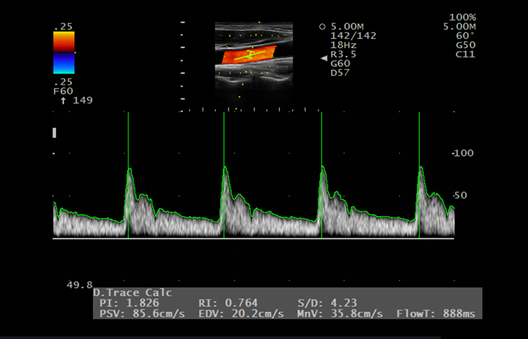

Sigue la forma de onda Doppler en tiempo real y muestra el valor medido. Dado que la congelación, la velocidad máxima y el valor de resistencia de los vasos sanguíneos (PI, RI) se muestran al mismo tiempo, es posible tomar mediciones más rápido.